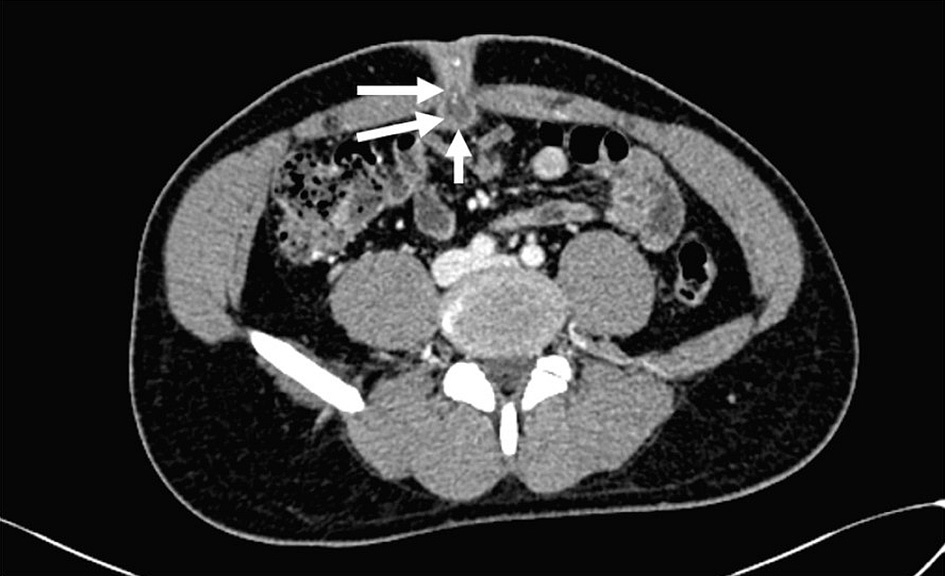

Laboratory investigations showed a normal white blood cell (WBC) count of 10 × 109/L and an elevated C-reactive protein (CRP) level of 5.6 mg/L. Renal and liver function tests were within normal parameters. The fasting plasma glucose was also within the normal range (5 mmol/L). During this consultation at the primary care clinic, a provisional diagnosis was an umbilical abscess, and the patient was referred for inpatient management, including intravenous antibiotics, imaging, and surgical evaluation. In the hospital, abdominal ultrasonography revealed an irregular hypoechoic collection within the rectus muscle and continuous with the subcutaneous tissue at the umbilical region, measuring approximately 2.2 × 2.7 × 1.9 cm. No intraperitoneal extension was demonstrated. Subsequent contrast-enhanced computed tomography (CT) of the abdomen and pelvis demonstrated a rim-enhancing fluid collection at the umbilicus measuring 2.1 × 1.7 × 1.7 cm, consistent with an infected umbilical urachal sinus (Fig. 2). Surrounding fat stranding was observed, indicative of localized inflammation. Additionally, the CT scan identified a vesicourachal diverticulum (Fig. 3a, b), characterized by a tubular tract extending from the anterior dome of the bladder towards the umbilicus.

Click for large image

Figure 2. Axial abdominal contrast-enhanced computed tomography image shows a blind ending, thick-walled, hypodense tubular collection (white arrows) extending posteriorly from the umbilicus into the abdominal cavity in keeping with an infected umbilical-urachal sinus.

When a urachal anomaly is suspected, Yiee et al recommend ultrasonography as the initial imaging modality due to its high sensitivity in detecting various types of urachal anomalies [12]. A urachal sinus typically appears on ultrasound as a tubular, hypoechoic structure that communicates exclusively with the umbilicus [17]. While ultrasonography serves as an accessible first-line modality for primary care providers, CT can be valuable in confirming or clarifying uncertain findings, particularly in the context of an infected umbilical urachal sinus. When ultrasound fails to yield a definitive diagnosis or when no umbilical drainage is observed, CT should be considered the next imaging step. CT imaging can help differentiate between a urachal cyst and other intra-abdominal pathologies, such as appendicitis or Meckel’s diverticulitis [12]. A CT scan will usually demonstrate a thickened and fusiform dilation of the urachus at the umbilical end, with no connection to the bladder [8]. In this case, both ultrasound and CT imaging were pivotal in establishing the diagnosis of an infected umbilical urachal sinus.